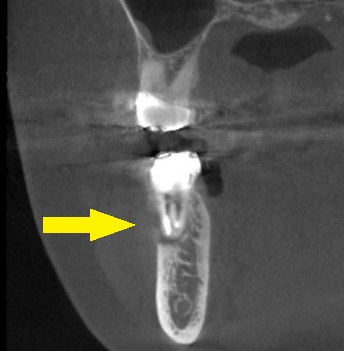

CTで見ると、頬側の骨が吸収されてしまっているので(下の2段目左)、抜歯して、治癒を待ってからインプラントの埋入を行うこととしました。

抜歯後4か月でCTを撮影してみると、骨の再生はありますが、一部は吸収されたままで、欠損が残っていました(下の写真2段目右)。